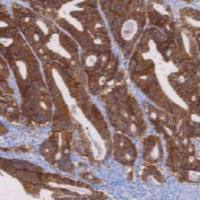

TLE1鼠抗人TLE1单克隆抗体

TLE1是TLE多基因家族中的一员,参与造血,神经元和末档上皮的分化。可在滑膜肉瘤中表达,在神经鞘瘤和多形性肉瘤中很少表达,有研究资料报道,TLE1在滑膜肉瘤中的表达的敏感性和特异性较Bcl2更高,因此被推荐作为滑膜肉瘤标志物。

- 阳性部位:胞核

- 适用组织:石蜡切片

- 预处理:热修复